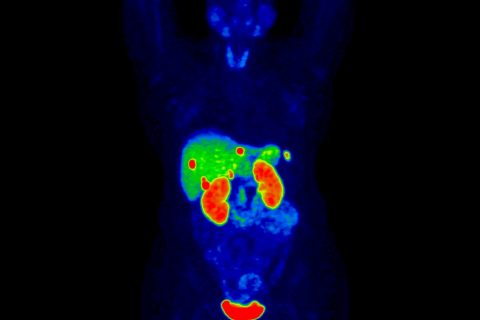

O PSMA11 (68Ga) é um radiofármaco utilizado em estudos de tomografia por emissão de pósitrons (PET) para avaliação de células com metástase de câncer de próstata. O exame é realizado com um antígeno de membrana específico da próstata (PSMA), essa proteína está localizada no tumor da próstata e, como consequência, nos focos de metástases.

Além de diagnosticar esses outros focos da doença, a tecnologia permite aos especialistas avaliarem como está sendo a evolução do tratamento do câncer.